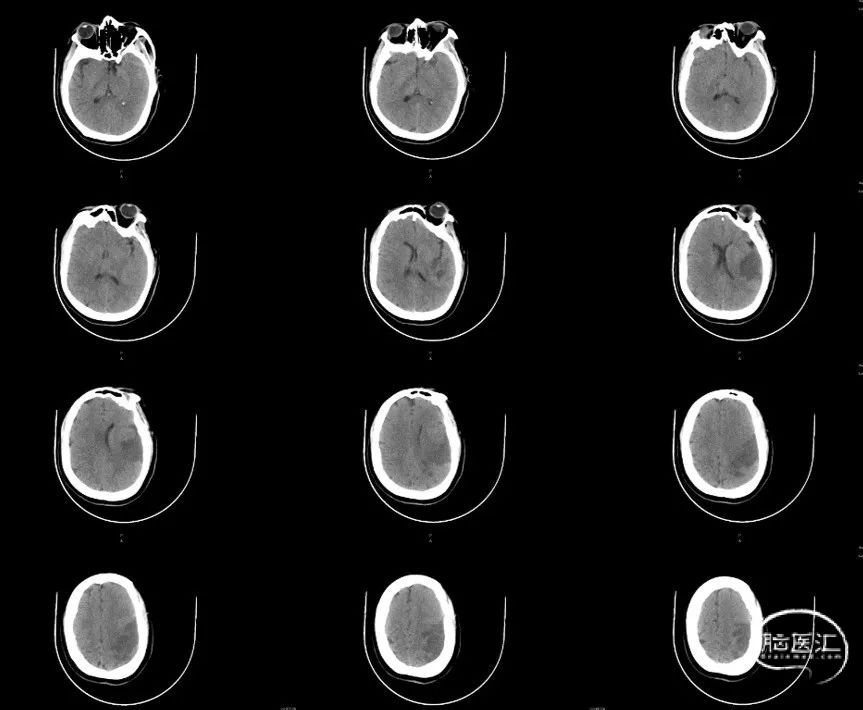

术后24h CT:

术后造影及CT提示:左侧颈内动脉开通,血流灌注达mTICI 2c级,造影剂无外渗,远端分支血管部分闭塞。

NIHSS评分变化:术后即刻NIHSS评分25分;术后24小时NIHSS评分13分;出院时NIHSS评分4分。